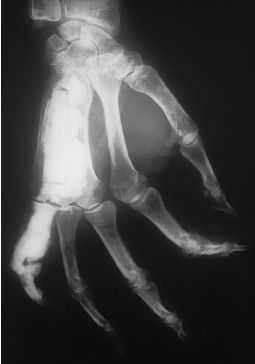

En la radiografía seaprecia una imagen densa, sin estructura alguna, con aspectomarmóreo que se localiza en la diáfisis del cuarto yquinto metacarpiano, y falange del quinto dedo de la mano derecha(fig. 1). Estos huesos aparecen deformados y como englobados en unamasa hiperostósica que recuerda a la cera derretida y parecesoldar el cuarto y quinto metacarpiano. Afecta tanto el periostiocomo el endostio (fig. 2). En el resto del estudioradiológico óseo no se encontraronalteraciones.

Figura1.

La imagen es compatible con unamelorreostosis, también conocida como enfermedad de Leri, yaque existe un defecto del desarrollo en la formaciónósea, tanto intramembranosa como endocondral. Eldiagnóstico diferencial debe realizarse con la artrogriposismúltiple, la displasia fibrosa y la osteopoiquilosis.Más raramente esta imagen puede aparecer en la osteomielitiscrónica y en los tumores óseos. Pero la falta deafectación de articulaciones y piel ayuda a sudiferenciación.